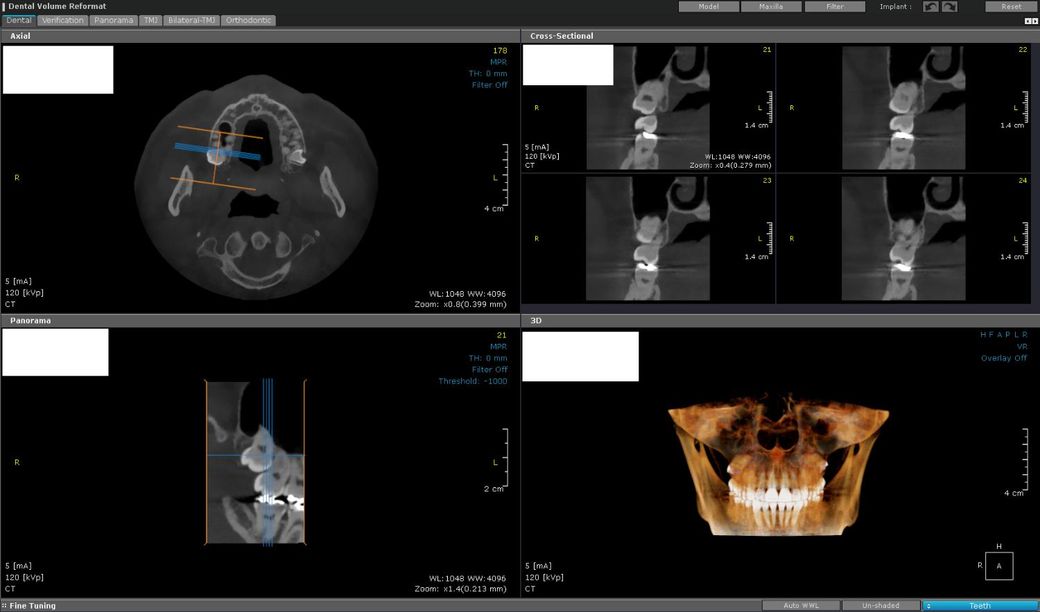

파노라마에선 9~10mm쯤이고 CT 왼쪽아래 가로로 36mm+-짜리가 사랑니같은데...

1.상악동에 사랑니가 박혀있는 상태인가요?

2.뽑을때 천공이 날까요?

3.천공이 난다면 대략 어느 정도 크기가 될까요?

4.뽑는 난이도와 위험이 어느 정도 되는 사랑니일까요?

5.천공 안나게 뺄 순 없나요? 밑에 잘라서 뿌리만 남긴다거나...

1. 사랑니 뿌리가 상악동안으로 들어가 있는 상태입니다.

2. 이미 천공되어 있는 상태이니 뽑은 후 천공은 불가피 합니다.

3. 천공 부위는 크지 않을 것으로 보입니다.

4. 난이도는 상으로 보면 됩니다.

5. 천공 안나게 할 수는 없으며 천공되어도 대개 저절로 막힙니다.

사랑니가 상악동막에 걸쳐 잇는것처럼 보입니다. 사랑니 발치 난이도는 어렵지 않습니다. 천공이 되더라도 시간이 지나면 자연스럽게 상악동막은 막아지니 너무 걱정하지마세요.